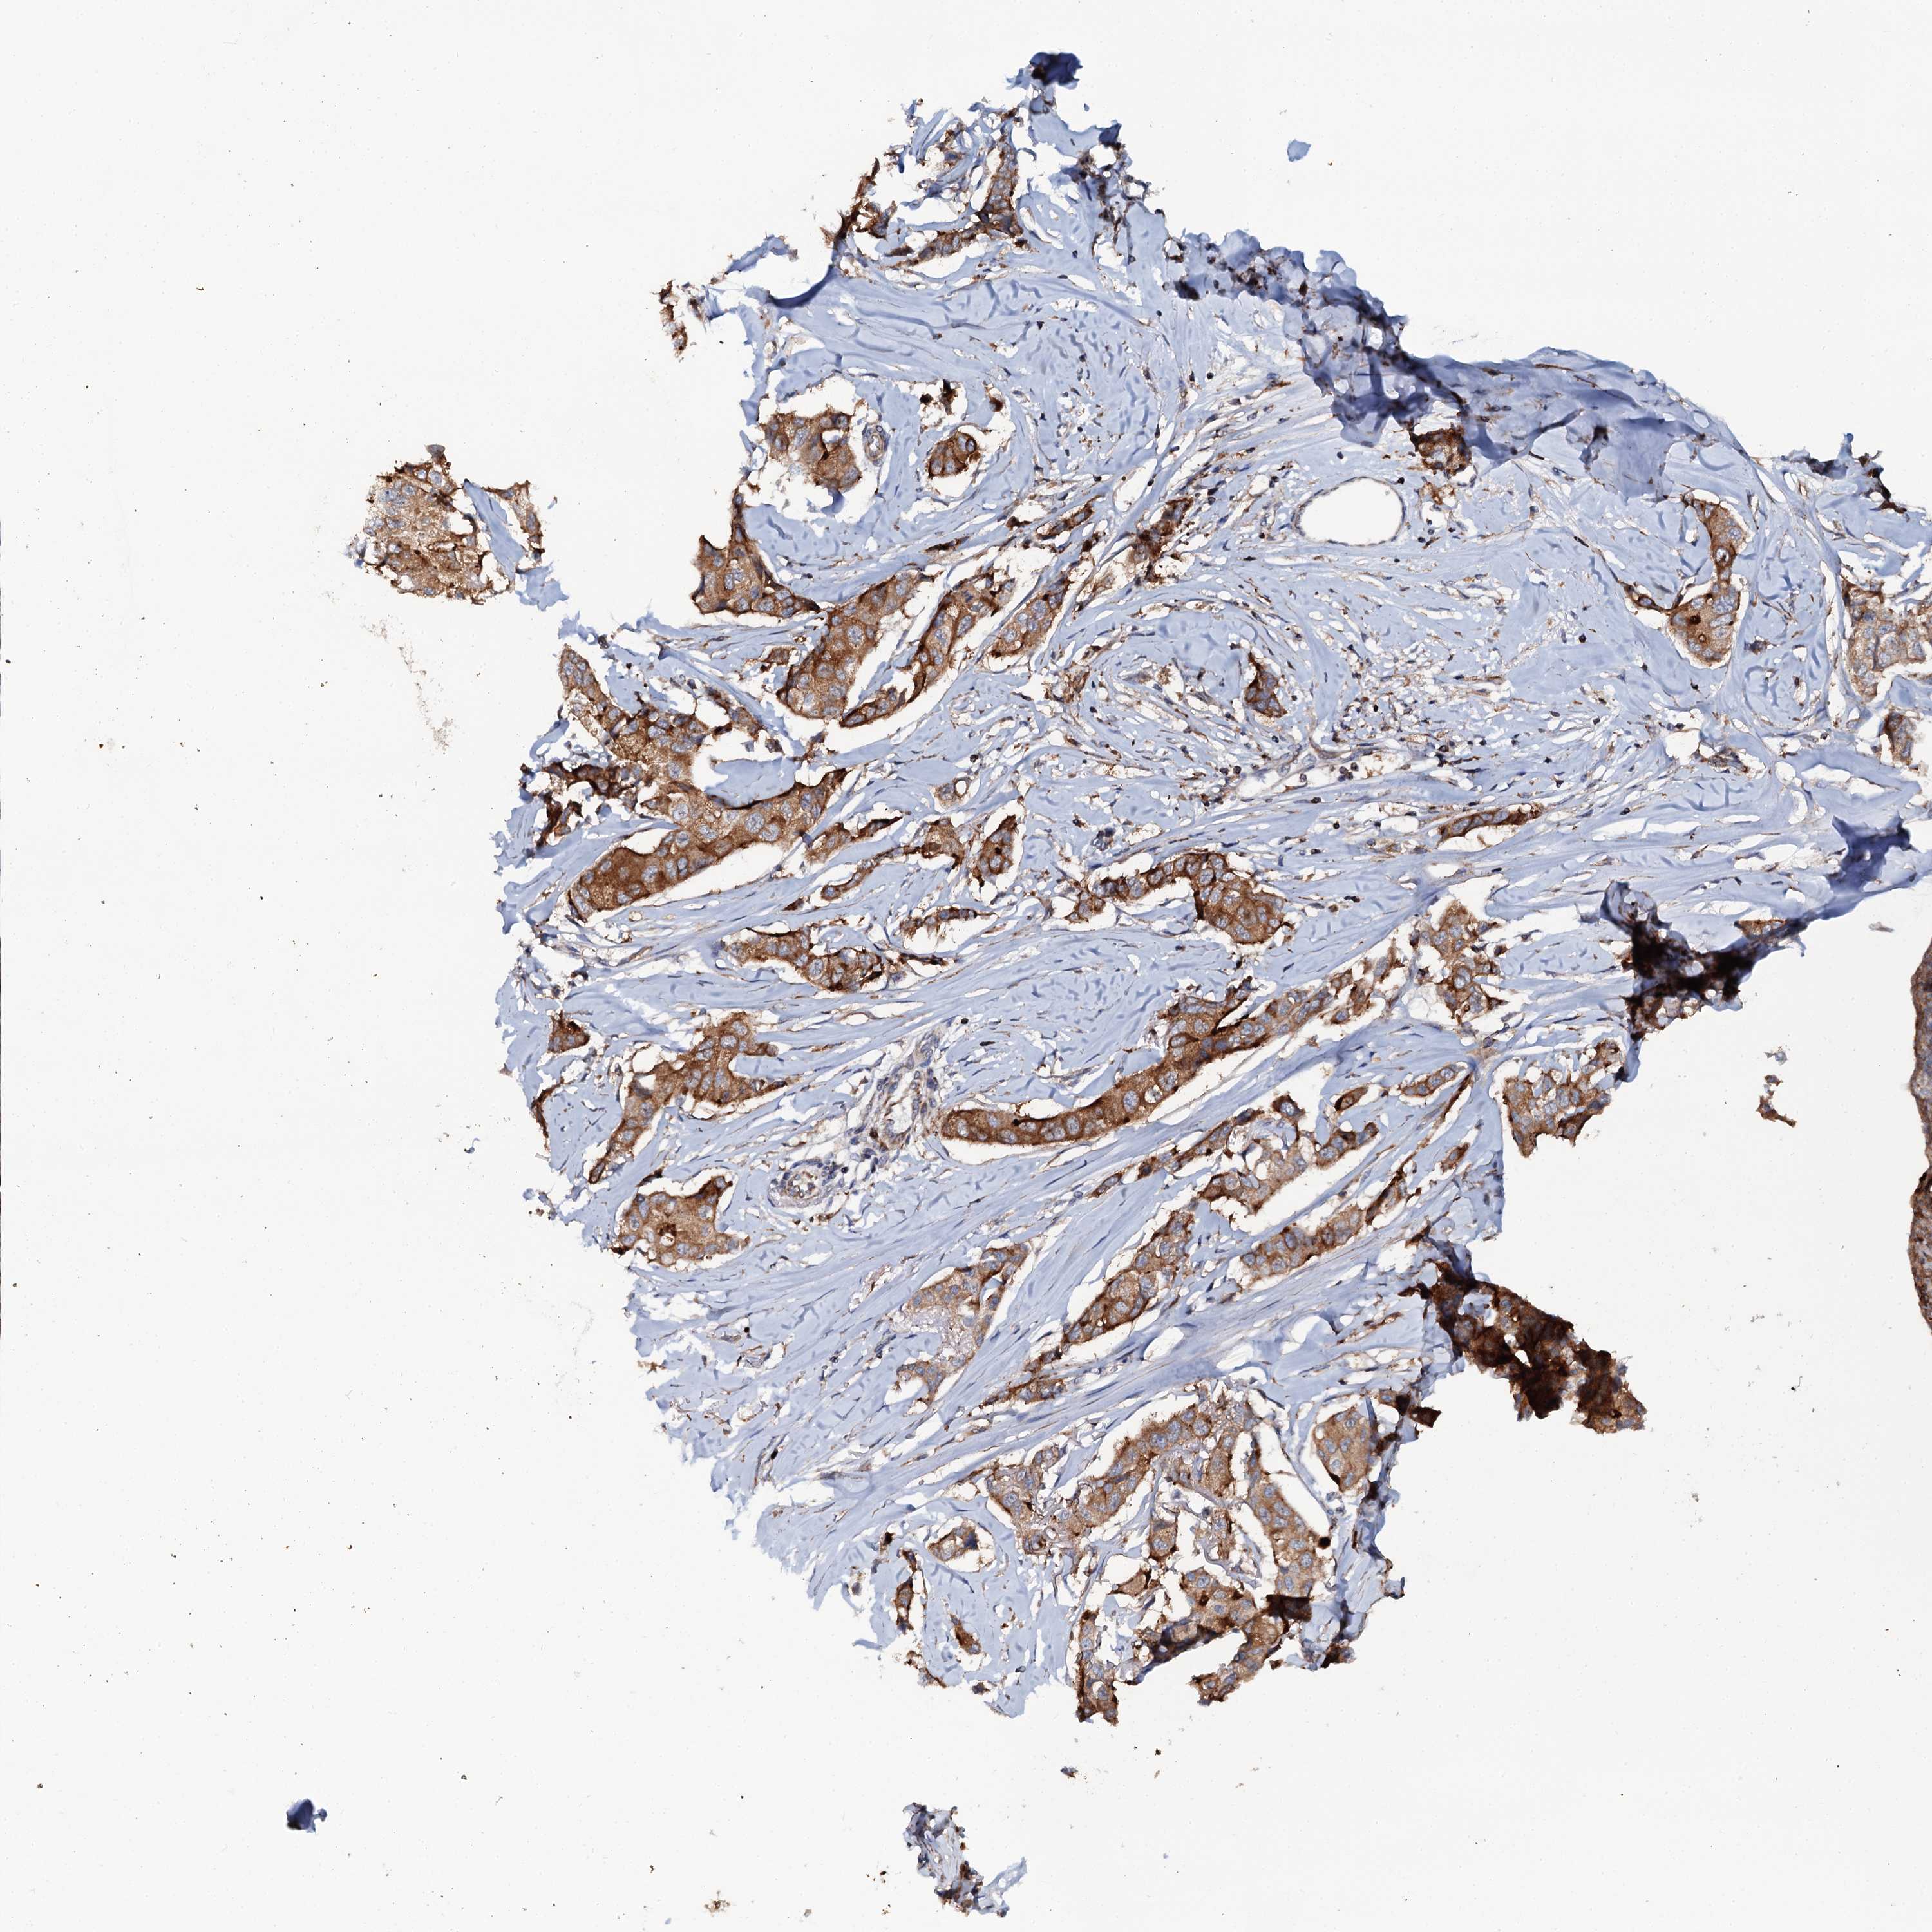

CANCER BREAST CANCER Show tissue menu

BRCA TCGA BRCA VALIDATION PROTEIN EXPRESSION

Breast cancer

Human cancer